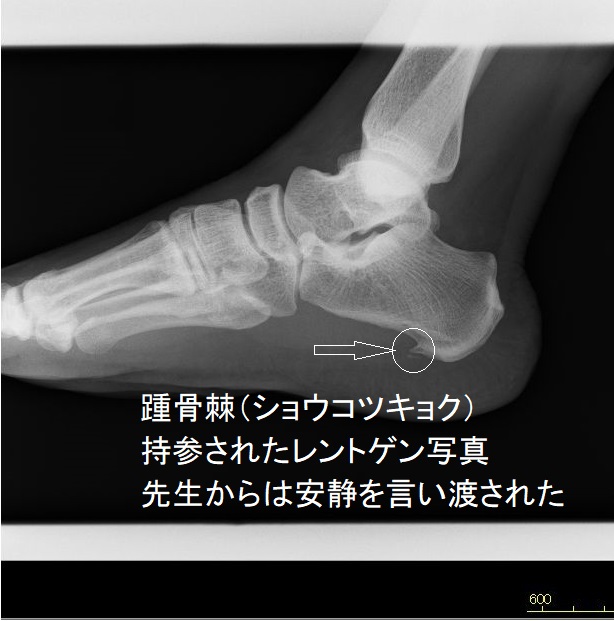

知ってほしい 踵骨棘

病院では、「踵骨棘」と診断を受け治療は特にないが安静にすることを勧められ、足の担当の方からは『タオルギャザー』を勧められた

痛みのある処は、レントゲンに示される骨棘のある辺りの様で棘の先の向いている角度に体重が乗ると激痛が走る